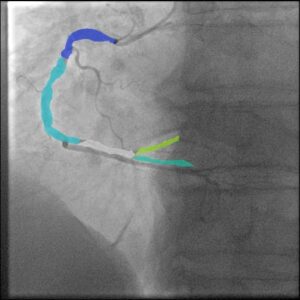

Con el uso de técnicas avanzadas de inteligencia artificial, doctorando en Ciencias de la Información de la Facultad de Informática Culiacán de la Universidad Autónoma de Sinaloa (UAS), desarrolló una metodología experimental para segmentar vasos sanguíneos y detectar estenosis coronaria a partir de imágenes de angiogramas, con el propósito de prevenir enfermedades cardíacas graves.

La investigación utilizó un conjunto de datos denominado ARCADE, generado en 2022 para un concurso internacional orientado al diagnóstico de problemas del corazón. A partir de esta base, se entrenaron modelos de aprendizaje profundo mediante la técnica YOLO (You Only Look Once), lo cual permitió segmentar imágenes en escala de grises para detectar con precisión tanto los vasos sanguíneos como las zonas críticas de estenosis.